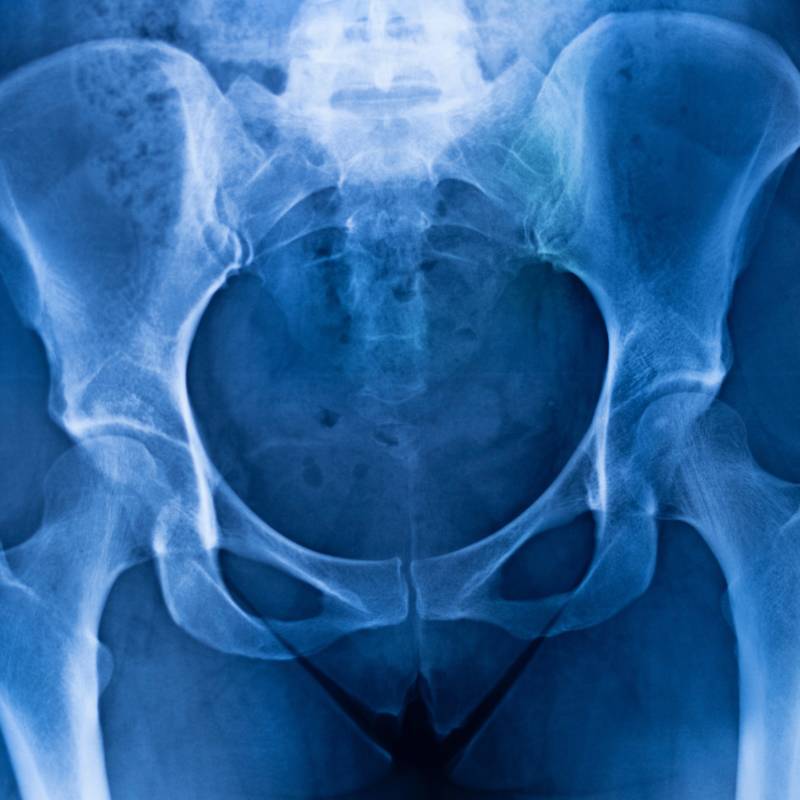

Sinar-X untuk menilai keadaan tulang punggung.

Sinar-X untuk memeriksa keadaan sendi pinggul.